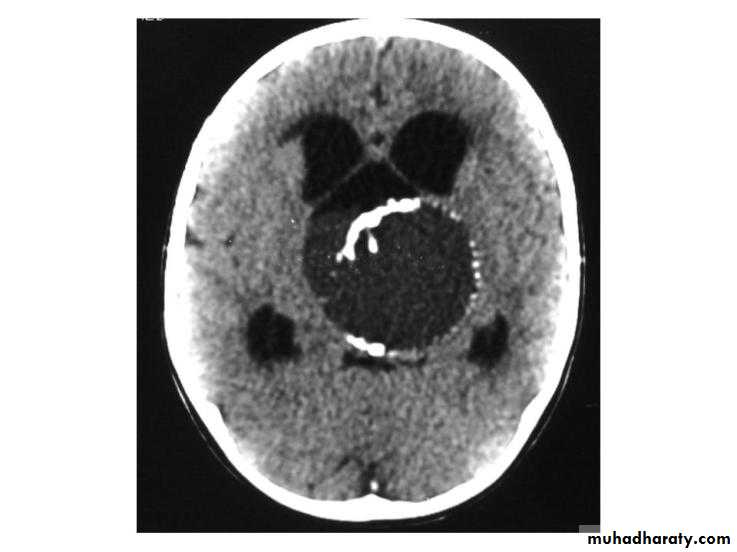

CRANIOPHARYNGIOMA CORONAL MRI

CRANIOPHARYNGIOMA CT-SCAN